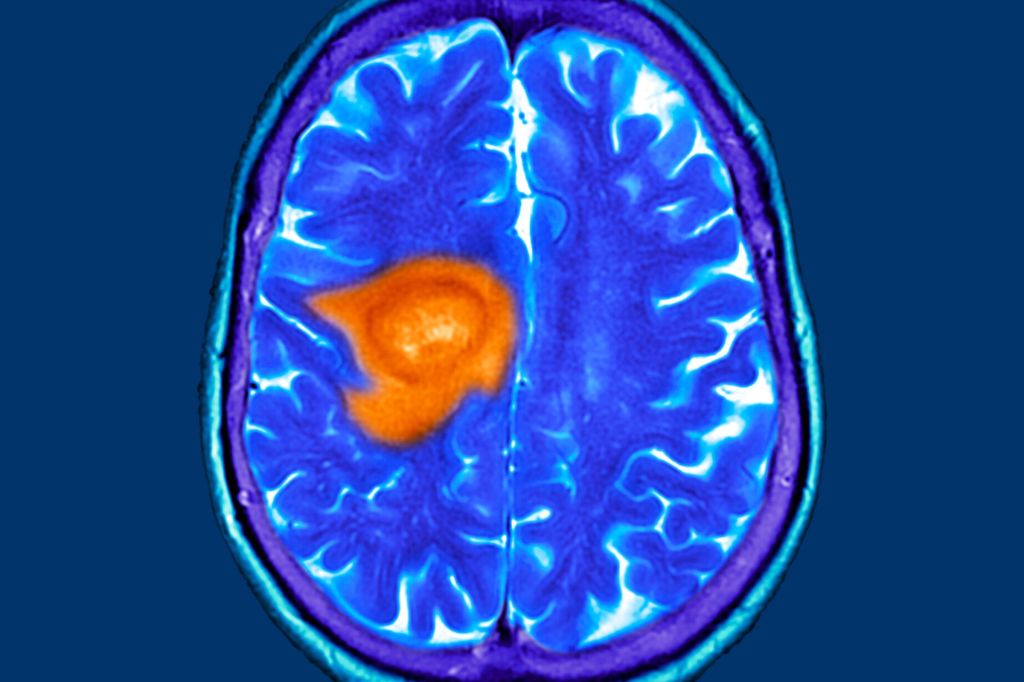

An experimental AAV gene therapy for treating glioblastoma

A $3.9 million award to Nicole Kristen Paulk, PhD, CEO and President of Siren Biotechnology will advance a novel adeno-associated virus (AAV) immuno-gene therapy for treating patients with glioblastoma, the most common primary brain tumor in adults and second in children.

Glioblastomas remain one of the deadliest brain cancers with a 5-year survival rate at 5 percent. There are more than 13,000 diagnoses of this type of cancer each year in the U.S.

This new therapy is designed to deliver a single-dose administration of engineered anti-cancer cytokine proteins directly to glioblastoma tumor cells through an AAV vector, a proven gene therapy vehicle. Following the delivery of cytokine proteins with an AAV, a patient’s immune system is triggered to fight and eliminate the tumor cells.

This award has the potential to bring direly-needed, effective therapies to the 1,400 Californians diagnosed with glioblastomas each year.